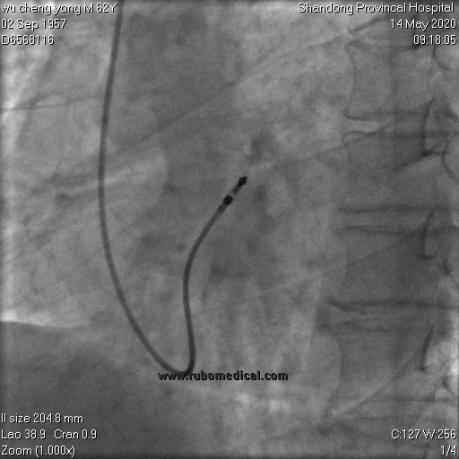

右心室主动电极植入后

右前斜以及左前斜位影像